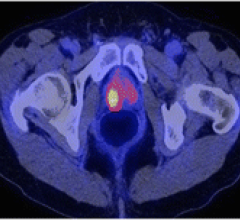

HealthMyne, an imaging informatics company, announced 510(k) clearance from the U.S. Food and Drug Administration (FDA). The new analytics software package is designed to provide radiologists with significant workflow efficiencies related to oncology cases, as well as advanced decision support.